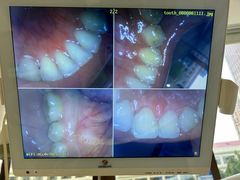

• 好大夫口腔(广州店)

• -好大夫口腔(广州店)